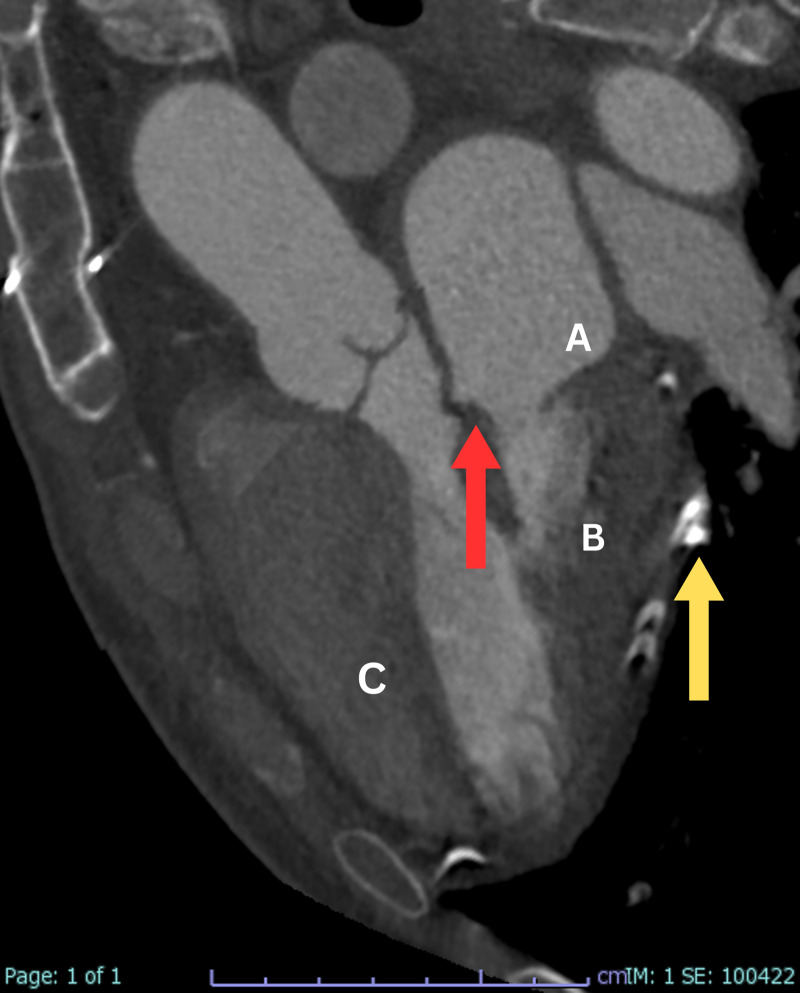

心包切除术后的显像:广泛残留的心包钙化和明显的二尖瓣增厚。

Unveiling Post-Pericardial Resection: Magnificent Imaging of Extensive Residual Pericardial Calcification and Impressive Mitral Valve Thickening.